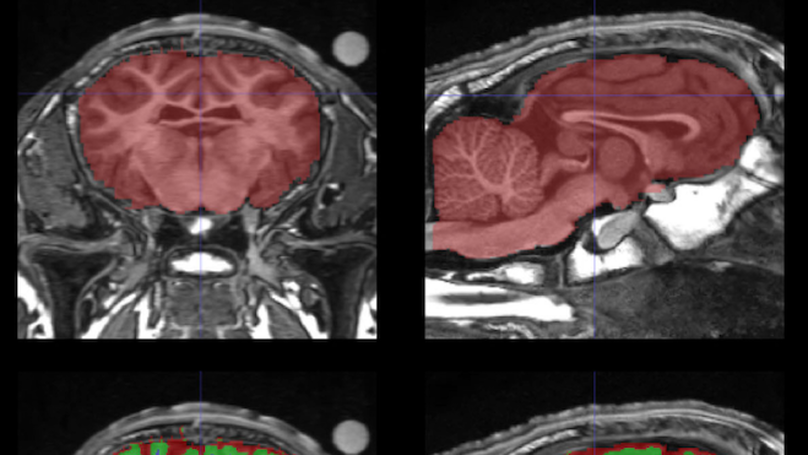

Magnetic resonance imaging (MRI) is a non-invasive technique that requires the participant to be completely motionless. To date, MRI in awake and unrestrained animals has only been achieved with humans and dogs. For other species, alternative techniques such as anesthesia, restraint and/or sedation have been necessary. Anatomical and functional MRI studies with sheep have only been conducted under general anesthesia. This ensures the absence of movement and allows relatively long MRI experiments but it removes the non-invasive nature of the MRI technique (i.e., IV injections, intubation). Anesthesia can also be detrimental to health, disrupt neurovascular coupling, and does not permit the study of higher-level cognition. Here, we present a proof-of-concept that sheep can be trained to perform a series of tasks, enabling them to voluntarily participate in MRI sessions without anesthesia or restraint. We describe a step-by-step training protocol based on positive reinforcement (food and praise) that could be used as a basis for future neuroimaging research in sheep. This protocol details the two successive phases required for sheep to successfully achieve MRI acquisitions of their brain. By providing structural brain MRI images from six out of ten sheep, we demonstrate the feasibility of our training protocol. This innovative training protocol paves the way for the possibility of conducting animal welfare-friendly functional MRI studies with sheep to investigate ovine cognition.

The psychoendocrine evaluation of lamb development has demonstrated that maternal deprivation and milk replacement alters health, behavior, and endocrine profiles. While lambs are able to discriminate familiar and non-familiar conspecifics (mother or lamb), only lambs reared with their mother develop such clear social discrimination or preference. Lambs reared without mother display no preference for a specific lamb from its own group. Differences in exploratory and emotional behaviors between mother-reared and mother-deprived lambs have also been reported. As these behavioural abilities are supported by the brain, we hypothesize that rearing with maternal deprivation and milk replacement leads to altered brain development and maturation. To test this hypothesis, we examined brain morphometric and microstructural variables extracted from in vivo T1-weighted and diffusion-weighted magnetic resonance images acquired longitudinally (1 week, 1.5 months, and 4.5 months of age) in mother-reared and mother-deprived lambs. From the morphometric variables the caudate nuclei volume was found to be smaller for mother-deprived than for mother-reared lambs. T1-weighted signal intensity and radial diffusivity were higher for mother-deprived than for mother-reared lambs in both the white and gray matters. The fractional anisotropy of the white matter was lower for mother-deprived than for mother-reared lambs. Based on these morphometric and microstructural characteristics we conclude that maternal deprivation delays and affects lamb brain growth and maturation.